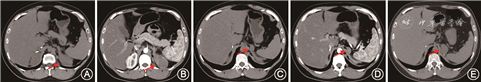

患者男,33岁,以“双肾上腺占位术后3个月”于2019年4月来北京协和医院内分泌科就诊。患者2010年体检发现右肾上腺占位,直径约4 cm,无不适。就诊于当地医院,相关检验、检查、诊断等不详,行右侧肾上腺肿物切除术,病理检查提示肾上腺皮质腺瘤,大小约3.8 cm×2.5 cm。患者术后无不适,未随诊。2018年11月行肾上腺CT发现左侧肾上腺低密度占位病变,约6.5 cm×3.8 cm×4.9 cm,中等强化(图1A、B);此外,左侧肾上腺内侧近结合部可见稍低密度结节,约2.6 cm×1.6 cm(图1C、D);患者无不适。病程中监测血压波动在120~130/80~90 mmHg(1 mmHg=0.133 kPa)。

实验室检查:血钠140 mmol/L,血钾4.0 mmol/L,血氯105 mmol/L,葡萄糖4.8 mmol/L。立位醛固酮 267.9 ng/L,立位肾素活性 5.44 ng·ml-1·h-1,醛固酮/肾素活性 4.9,早8点促肾上腺皮质激素(ACTH)为55.2 ng/L,血总皮质醇为76.8 μg/L,24 h尿游离皮质醇 49.20 μg,24 h尿儿茶酚胺未见异常。睾酮、孕酮、17α羟孕酮未查。生长抑素受体显像提示肾上腺占位生长抑素受体高表达,考虑神经内分泌肿瘤可能性大。肾上腺髓质显像未见异常。于2019年1月行左肾上腺较大占位性病变切除,手术保留部分肾上腺,未切除较小占位性病变。术后病理符合肾上腺皮质腺瘤,大小7.5 cm×6.0 cm×3.5 cm。免疫组织化学:Melan-A(+),Vimentin(+),α-inhibin(+),CgA(-),Syn(+),Ki-67(index 10%),CD34(-)。术后规律随诊。2019年4月复查肾上腺CT(图1E),提示未切除的较小病灶较前增大(3.5 cm×2.6 cm),于是进一步就诊于北京协和医院内分泌科。